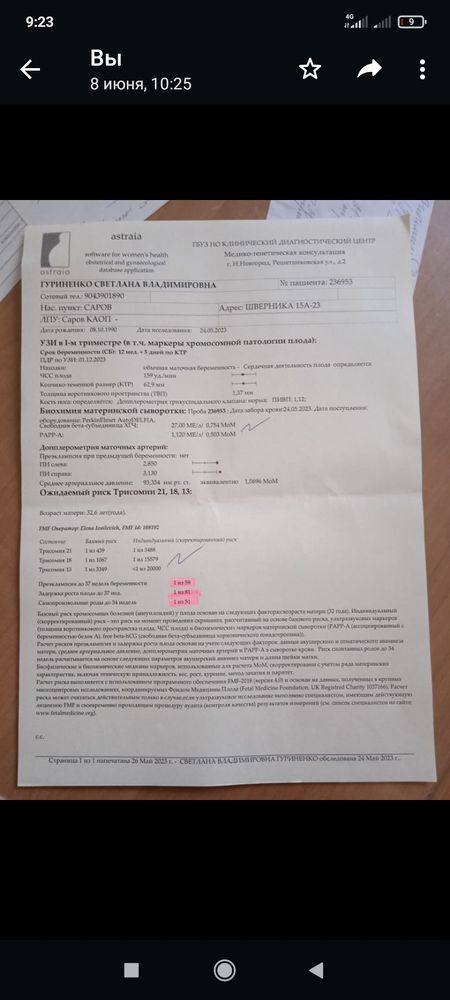

К этому врачу на это время уже пришли пациенты... Начали разбираться а меня записали не на 23 мая а на 23 июня🥴Муж после операции на колено, рулил такое расстояние, я думала нас отправят ни с чем.. Но предложили осмотр у другого врача, кмн,стаж 36 лет, я конечно расстроилась но согласилась. Василёк наш тоже видимо был не настроен показывать себя как надо и как бы мы не старались, что бы мы не делали, в профиль он не лёг, кувыркался швырялся но в профиль нет, в итоге кость носа осматривали с лица, складку(твп) вообще не знаю с какой стороны, зато торчок показал во всей красе 🙈врач сказала если не отпадёт мальчик будет 🤞🙌тут конечно я расплылась.... Появилась надежда что наша мечта о сынуле всё таки осуществится🙏Я с 9 утра до сдачи крови в 5 вечера была голодная(ещё и с ночной смены на ногах не спамши🤪),кровь сдала, попросила горячего чая, пока ждали заключения, всё хорошо, риски низкие, фото в этот раз мы красивые не получили, Василёк и там не поддался🤪А сегодня в городе я прошла скрининг по омс, на УЗИ меня опять крутили вертели, ну не хочет дитя что бы его разглядывали, вроде тоже всё хорошо, правда кровь недели через 2 с рисками, но я уже особо не жду, но пусть будет. Врач в конце, пол могу сказать если хочешь узнать, я говорю там торчок☺она говорит да, там мальчик 🙏Я пока сильно не обольщаюсь, но очень хочу что бы у нас и не отпало и не рассосалось ничего и моё материнское сердце немного залечит наш маленький сынок о котором мы с папой так мечтаем🙏🙏🙏но главное что бы живыми здоровыми и в срок 🙏💫

Ксю, вот результат в жц и пометки врача что в норме а что нет🙂кровь норма

Ксю, вот результат в жц и пометки врача что в норме а что нет🙂кровь норма